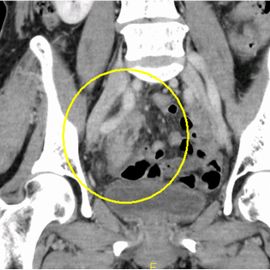

[慢性虫垂炎(急性増悪)] 手術:単孔式腹腔鏡下回盲部切除術

下腹部痛と軟便のため来院。血液検査にてCRP値、白血球数ともに高値を認め、精査の結果、慢性虫垂炎

および虫垂腫瘍疑いと診断した。症状の憎悪も認め、単孔式腹腔鏡下回盲部切除術を施行した。

CT画像